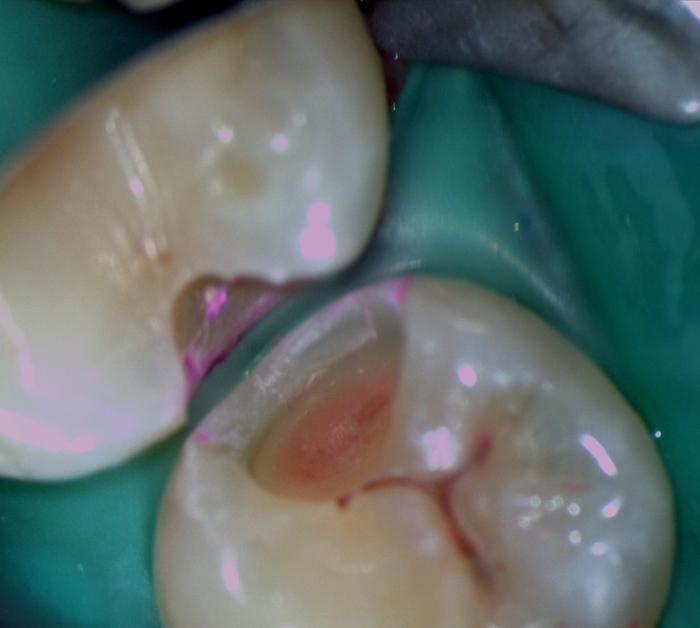

Если доктор уберёт слой эмали, то можно эти полости увидеть:

Очищенный от инфицированных тканей зуб выглядит так:

А это - они уже пролечены.